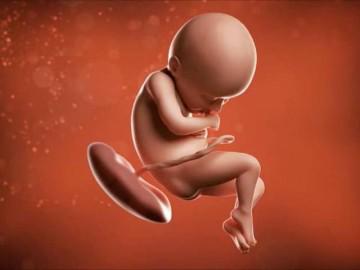

Thai nhi 36 tuần tuổi có cân nặng khoảng 2,7 - 2,75 kg (như một quả dưa vàng) và chiều toàn thân đạt khoảng 47cm (chiều dài từ đầu đến mông khoảng 33 -34 cm).

Ở tuần 36 thai kỳ, khuỷu tay, chân và đầu bé có thể nổi lên trên bụng của người mẹ khi bé “vươn vai” hay chuyển động. Khuôn mặt bé trông khá bầu bĩnh, một phần do các lớp mỡ và một phần do sự phát triển mạnh của các cơ mút.

Thai nhi 36 tuần tuổi.

Lúc này thành tử cung và thành bụng bạn đang giãn hết cỡ, ngày càng mỏng hơn, đây là cơ hội để bé học hỏi và làm quen với nhịp sinh học ngày và đêm do ánh sáng đã có thể xuyên qua thành bụng chút ít. Thai nhi cũng bắt đầu đùa nghịch với các ngón tay, chân. Thận đã phát triển hoàn thiện và gan cũng đã bắt đầu thực hiện chức năng lọc thải.